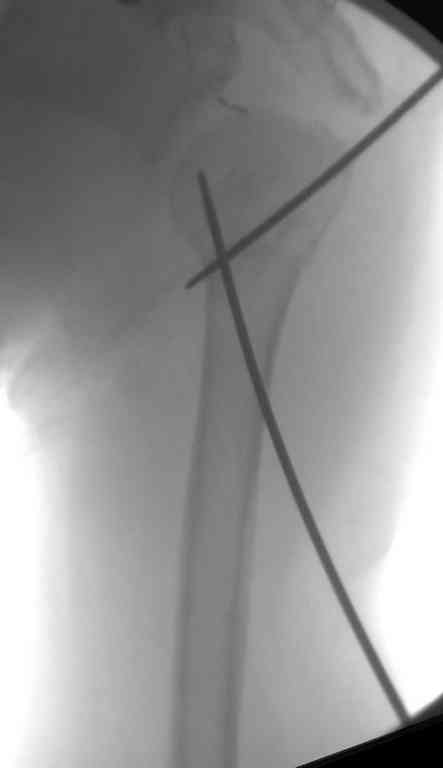

Неправильно выбранная тактика по фиксации или технические ошибки во время операции могут привести к серьезным осложнениям. Здесь привожу

пример из нашей практики, вроде обычный перелом шейки, фиксированный популярным методом "Сиэтла" - множественными спицами 2.8 мм с резьбой на конце.

При первичном осмотре в поликлинике через 3 недели обнаружили миграцию двух спиц, срочно госпитализированному на второй день перед операцией на всякий случай сделали снимок, одна спица находилась под ключицей в шейном отделе (на снимке).